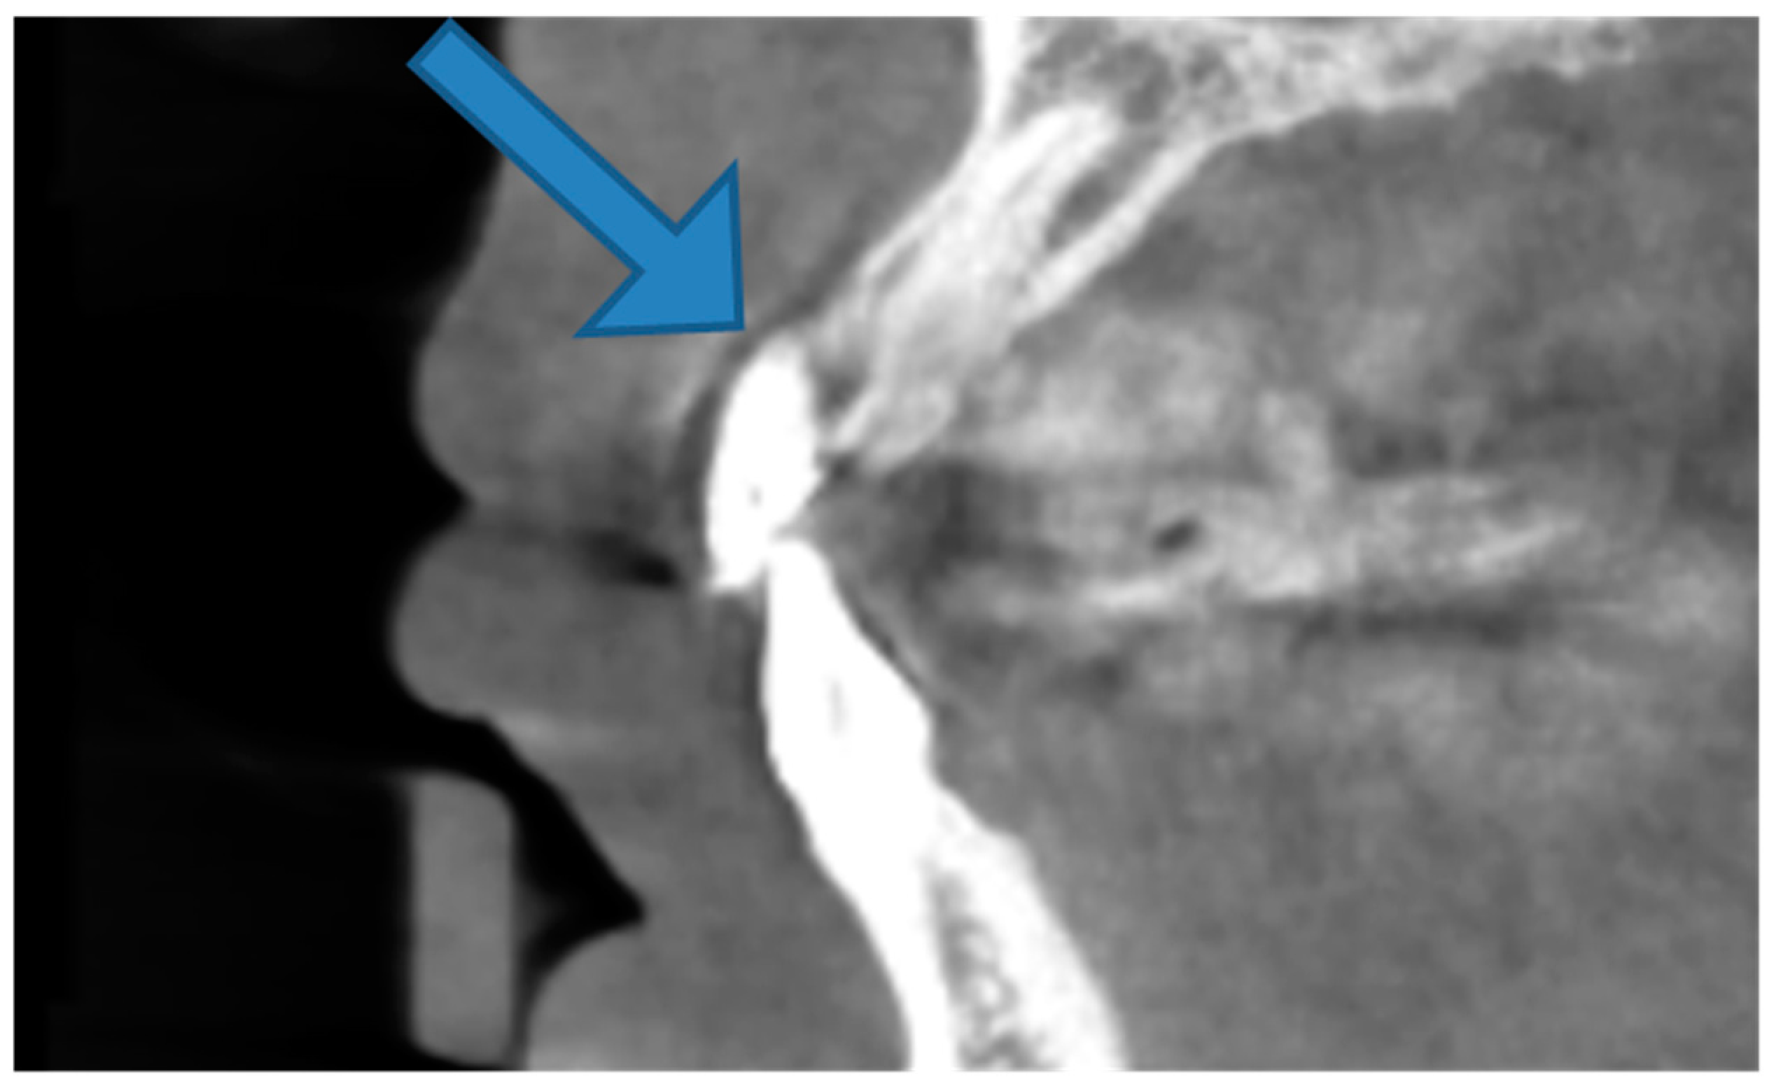

2.2. Radiographical Examination